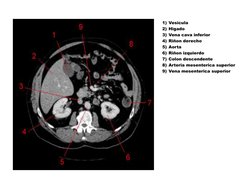

Vesicula

Higado

Vena cava inferior

Rion derecho

Aorta

Rion izquierdo

Colon descendente

Arteria mesenterica superior

Vena mesenterica superior